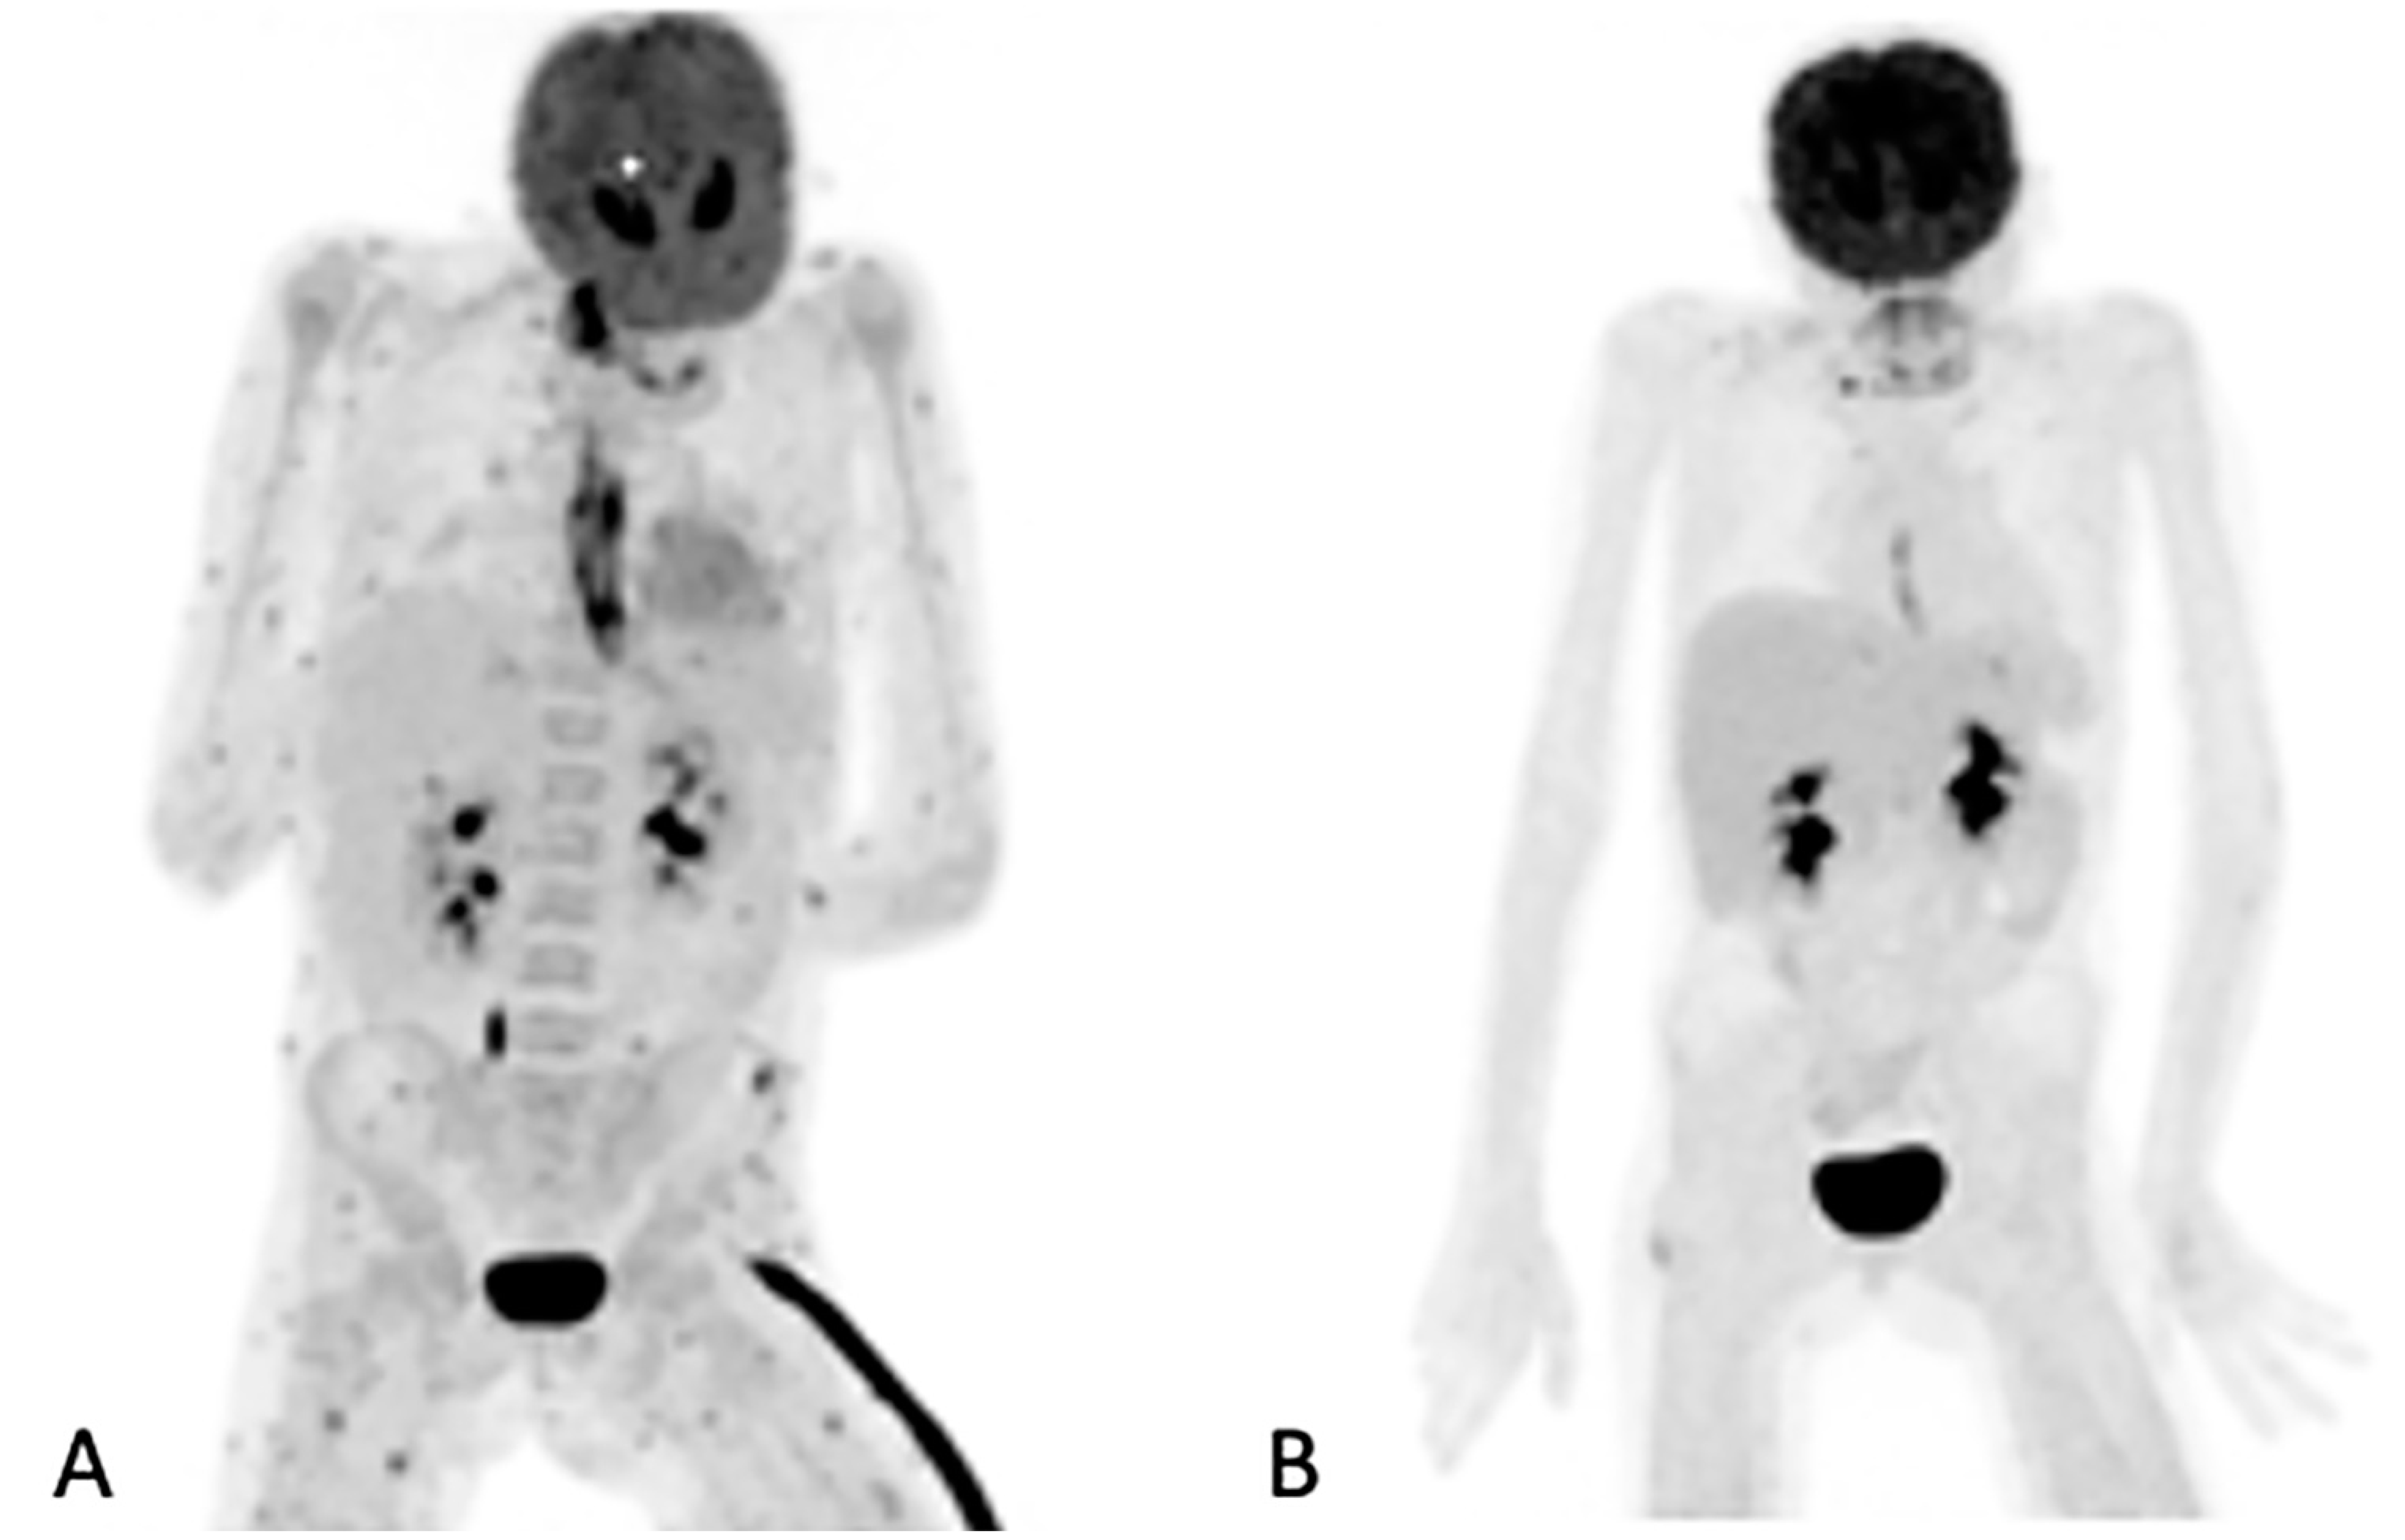

In the 32 patients that had repeated [18F]FDG PET/CT imaging to assess the responses, the follow-up helped the clinicians to decide to stop, continue or change antifungal therapy (Figure 3). [18F]FDG PET/CT detected previously unknown IFI lesions in five patients of the 18 that were referred for the staging of the infection, which led to therapy prolongation in four and a change in therapy in one. In the 10 patients with indications of unexplained fevers or increasing infective markers, [18F]FDG PET/CT was found to be useful in four patients, as it guided the biopsy that led to the diagnosis of the IFI (see Figure 4). In the seven patients that were being prepared for ASCT, [18F]FDG PET/CT was considered to add value for all. In four patients, the [18F]FDG PET/CT allowed clinicians to proceed with the procedure; in two others, further antifungal therapy was provided with follow-up with [18F]FDG PET/CT, and a biopsy was conducted in one of the patients before ASCT was performed. Finally, in the six patients where scans was performed to assess metabolic activity in residual anatomic lesions, [18F]FDG PET/CT was considered useful. There was a complete metabolic response in five patients, and in two patients, further antifungal treatment was instituted. Table 5 tabulates the patients for which [18F]FDG PET/CT was deemed to have added value. Figure 4 shows a female patient with acute myeloid leukemia while on antifungal therapy, where [18F]FDG PET/CT explained the increasing infective markers by demonstrating multiple IFI lesions outside the thorax.

Figure 4.

Sixty-three-year-old female with acute myeloid leukemia on treatment for pulmonary aspergillosis. [18F]FDG PET/CT was performed because there was unexplained fever, and the IFI lesions seen on HR CT (A) were similar to in the HR CT scan performed a month and 2 months earlier. [18F]FDG PET/CT scan (B) showed multiple IFI lesions outside the thorax, providing an explanation for the persistent fever.